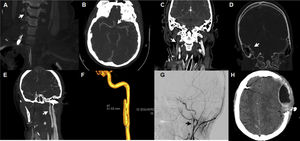

La severidad de la LCVT se define por la escala de gravedad de Denver (también llamada escala de Biffl), que está diseñada para orientar el enfoque terapéutico y pronosticar resultados4. Sin embargo, esta escala solo define las lesiones que se producen a nivel arterial dentro de lo que es el esquema habitual de la LCVT, dejando de lado las lesiones venosas sobre los senos cerebrales, las cuales pueden también acompañarse de déficits neurológicos5. Nosotros presentamos 5 casos, de los cuales 3 mostraron lesiones arteriales con una severidad de grado ii, iii y iv (fig. 1A, B, E, F y G) y 2 casos lesión de senos venosos cerebrales (fig. 1C y D).

Aspectos radiológicos de los pacientes con lesión cerebrovascular traumática. A: disección de arteria vertebral derecha con imagen arrosariada y buen flujo distal (tipo i de Denver). B: disección de arteria carótida interna supraclinoidea izquierda, flujo filiforme (tipo iv de Denver). C: trombosis seno venoso transverso y vena yugular derecha. D: trombosis venosa seno sigmoideo derecho. E: disección de arteria carótida izquierda con desarrollo de pseudoaneurisma (tipo iii de Denver). F: arteriografía con reconstrucción 3D de pseudoaneurisma (3cm de eje longitudinal) en el segmento extracraneal posbulbar de arteria carótida izquierda. G: disección del segmento extracraneal posbulbar con la presencia de 2 pseudoaneurismas en arteria carótida interna derecha. H: hematoma epidural hiperagudo tras inicio de anticoagulación.

El objetivo terapéutico es evitar el desarrollo de lesiones isquémicas3. Se han demostrado beneficios en la morbimortalidad con la terapia antitrombótica precoz4; a pesar de ello, existe discrepancia sobre cuál tratamiento antitrombótico es más adecuado (anticoagulación o antiagregación)7. El riesgo de eventos isquémicos aumenta según la gravedad de la lesión; por tal motivo, las recomendaciones actuales orientan a iniciar un tratamiento antitrombótico tras el diagnóstico, considerando el riesgo hemorrágico3,4,8. En nuestra serie, 4 pacientes recibieron anticoagulación con heparina no fraccionada y uno con heparina de bajo peso molecular. Un paciente presentó resangrado (fig. 1H) al quinto día de inicio de la terapia anticoagulante con heparina no fraccionada. En el momento actual no hay ensayos clínicos que orienten la terapia antitrombótica inicial. Ninguna terapia, al compararse entre ellas, ha demostrado menor incidencia en el desarrollo de lesiones isquémicas, aunque la mayoría de los estudios son de baja calidad y tienen un alto riesgo de sesgo7. A pesar de todo esto, se tiende a recomendar el uso de heparina no fraccionada por su reversibilidad, lo cual es fundamental en la etapa aguda, y combinarlo con una posterior modificación a tratamiento antiagregante3,7,9. En cuanto a aquellos pacientes con lesiones isquémicas establecidas, el tratamiento antitrombótico tampoco está claro. No existe evidencia de que la doble terapia antiagregante sea más efectiva que el régimen con un solo fármaco3.